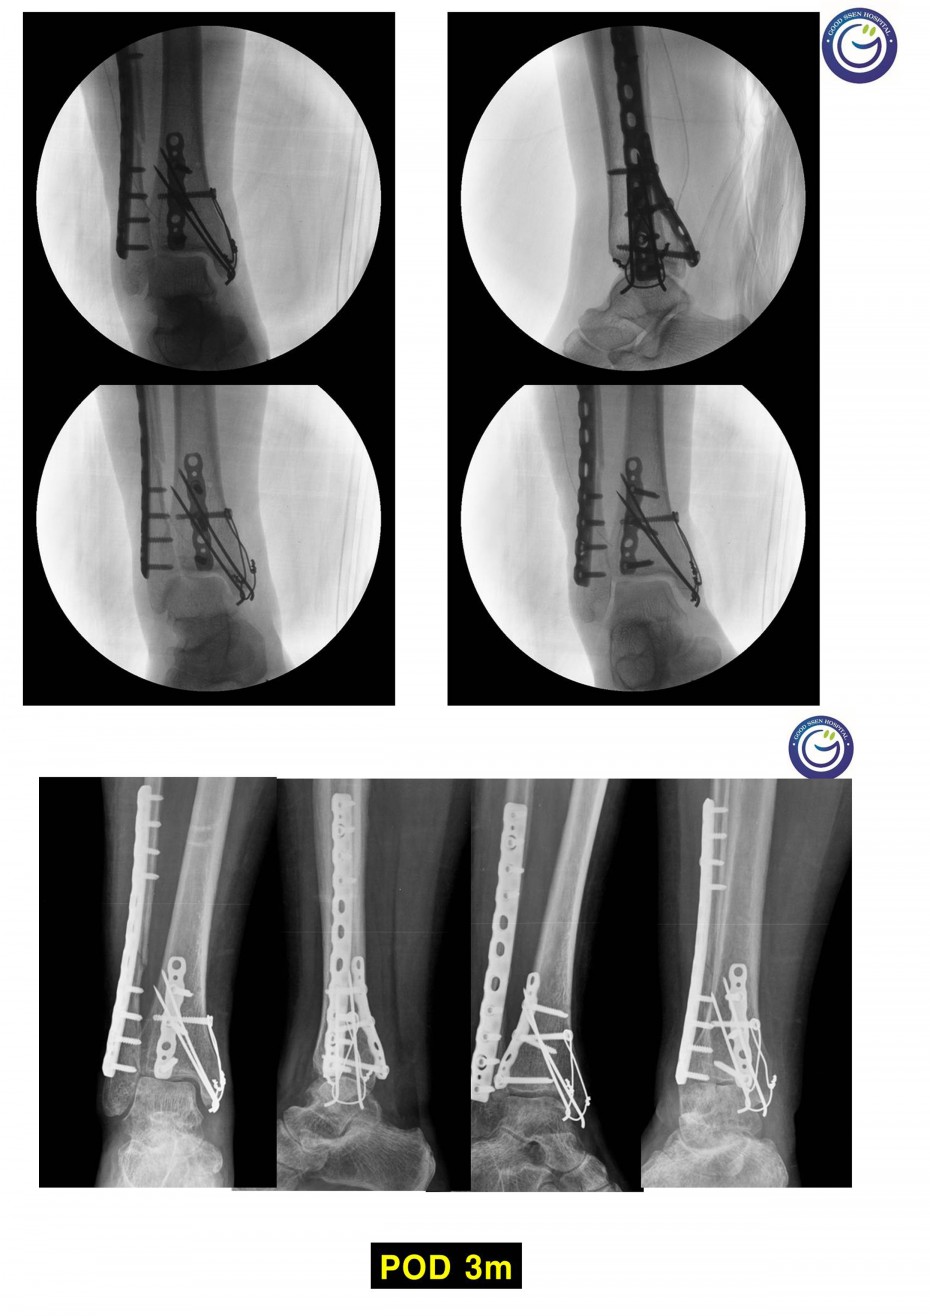

관절을 침범하는 심한 분쇄골절

절개없이 고정하는 최소침습적 고정방법 (MIPO)